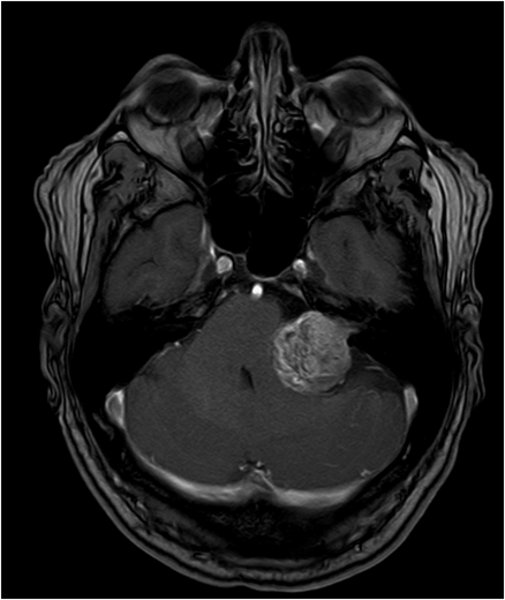

Akustikusneurinom T2 - axial - Vergrößerung

Akustikusneurinom T1 mit KM - axial